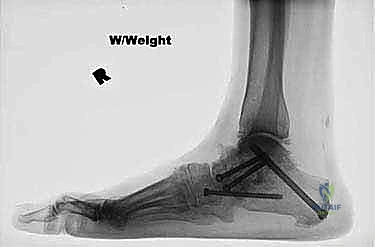

- All talonavicular and subtalar joints healed ( FIG 4 ).

Radiographic Correction Was Comparable To Previous Series Describing Traditional Two-Incision Triple Arthrodesis.

In a cadaver study, 90% of the calcaneocuboid joint articular surface was able to be prepared successfully from the medial incision.

- Two of the 17 patients (12%) developed a nonunion of the calcaneocuboid joint. Neither of these was symptomatic.

Seventeen patients underwent single-medial-incision triple arthrodesis.

All 17 demonstrated clinical improvement in alignment and pain relief.

FIG 4 • After single-medial-incision triple arthrodesis, the patient shown in Figure 3 had excellent correction of her deformity without wound-healing complications.

B